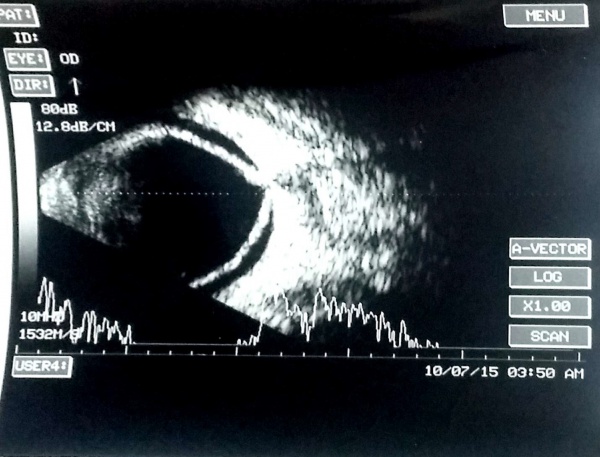

A PVD is usually a thin wavy membrane which moves freely with ocular movements.

Vitreous hemorrhage reveals multiple mobile point echoes in the vitreous cavity. The amplitude of such point echoes is usually mild to moderate. In cases of vitreous hemorrhage due to proliferative retinopathies (e.g., proliferative diabetic retinopathy, retinal vasculitis), it is also necessary to localize the area of neovascularization/fibrovascular proliferation. The areas of neovascularization (NV) are denoted by areas of strong vitreoretinal adhesion, the PVD is attached to the NV in a 'v' shaped configuration. In vitreous hemorrhage related to a PVD-induced retinal tear, a PVD is obvious in the USG. Also, the anterior extent of the PVD may be seen attached to the anterior flap of retinal tear. In old patients with evidence of age-related macular degeneration in the fellow eye, it is necessary to rule out a large choroidal neovascular membrane with subretinal bleed and breakthrough bleeding into the vitreous.

Note the after-movements of the PVD in this patient with subhyaloid hemorrhage and vitreous hemorrhage.